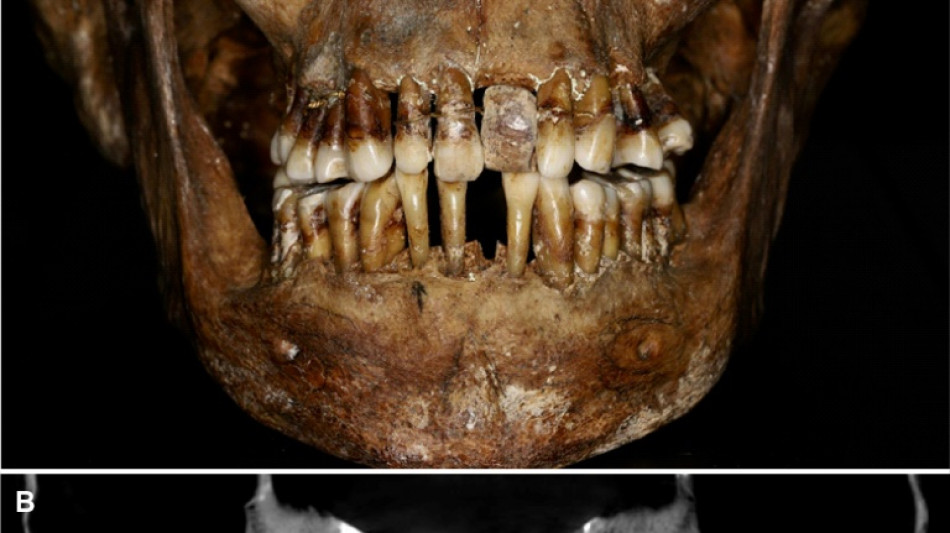

La dentition d'une aristocrate du XVIIe siècle comme marqueur social / Photo: Handout - INRAP/AFP

La sépulture d'Anne d'Alègre, morte en 1619 à l'âge de 54 ans, avait été déterrée lors d'une fouille au château de Laval, en 1988. Embaumé dans un cercueil de plomb, le squelette était particulièrement bien conservé, sa dentition aussi.

Plus de trente ans après, une équipe comprenant des archéologues et des dentistes dévoile qu'Anne d'Alègre était atteinte d'une maladie parodontale qui provoque le déchaussement progressif des dents, selon une étude parue cette semaine dans Journal of Archeological Science.

Les images radiologiques par "Cone Beam", un scanner en 3D, montrent que la patiente portait une prothèse dentaire remplaçant une incisive, soutenue par des fils d'or, ainsi qu'une ligature de contention sur des pré-molaires.

Des examens en macroscopie ont déterminé que cette prothèse était en ivoire d'éléphant, écartant la piste de l'ivoire de dents d'hippopotame, également utilisé à l'époque.

A long terme, ce traitement, ainsi que les "multiples resserrages nécessaires, ont entraîné l'instabilité des dents voisines", détaille l'Inrap.